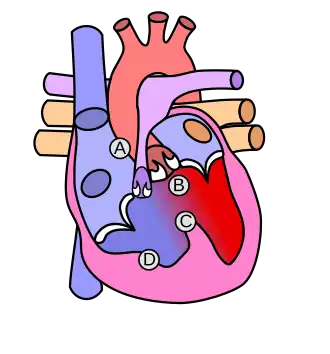

Cardiopatías

Entre un 40 y un 50% de los recién nacidos con SD presentan una cardiopatía congénita, es decir, una patología del corazón presente en el momento del nacimiento,[34] y esta es la causa principal de mortalidad en niños con SD. Algunas de estas enfermedades solo precisan vigilancia para comprobar que su evolución es adecuada, mientras que otras pueden necesitar tratamiento quirúrgico urgente. Casi la mitad de ellas se corresponden con defectos del septo aurículo-ventricular (ausencia de cierre más o menos completa de la pared que separa aurículas y ventrículos). Una tercera parte (en torno al 30 % según las fuentes) son defectos de cierre del septo ventricular (pared que separa los ventrículos entre sí), y con menos frecuencia se encuentran otras enfermedades como ostium secundum,[35] ductus arterioso persistente[36] o tetralogía de Fallot.[37]

En general casi todos estos defectos provocan paso inapropiado de sangre desde las cavidades izquierdas del corazón a las derechas, lo que aumenta la circulación pulmonar. La tetralogía de Fallot, en cambio, provoca un cortocircuito inverso, por lo que disminuye el flujo sanguíneo pulmonar y aparece cianosis (color azulado por la deficiente oxigenación de la sangre), sobre todo en crisis de llanto o esfuerzos. Esta es una patología grave que precisa cirugía, habitualmente en el primer año de vida, para reparar los defectos. Es frecuente que el examen clínico del recién nacido no ofrezca datos de sospecha por lo que pueden quedar sin diagnosticar en la etapa neonatal hasta un 50 % de los recién nacidos con cardiopatía congénita. Por este motivo se recomienda la realización de una ecografía del corazón a todo recién nacido con SD.[38] En la etapa de adolescencia o adulto joven pueden aparecer defectos en las válvulas cardíacas (Con mayor frecuencia, prolapso de la válvula mitral). Los adultos con SD presentan, en cambio, menor riesgo de arterioesclerosis y unas cifras de tensión arterial inferiores a las de la población general, por lo que se consideran un grupo poblacional protegido frente a enfermedad coronaria (angina de pecho, infarto de miocardio…).[39]